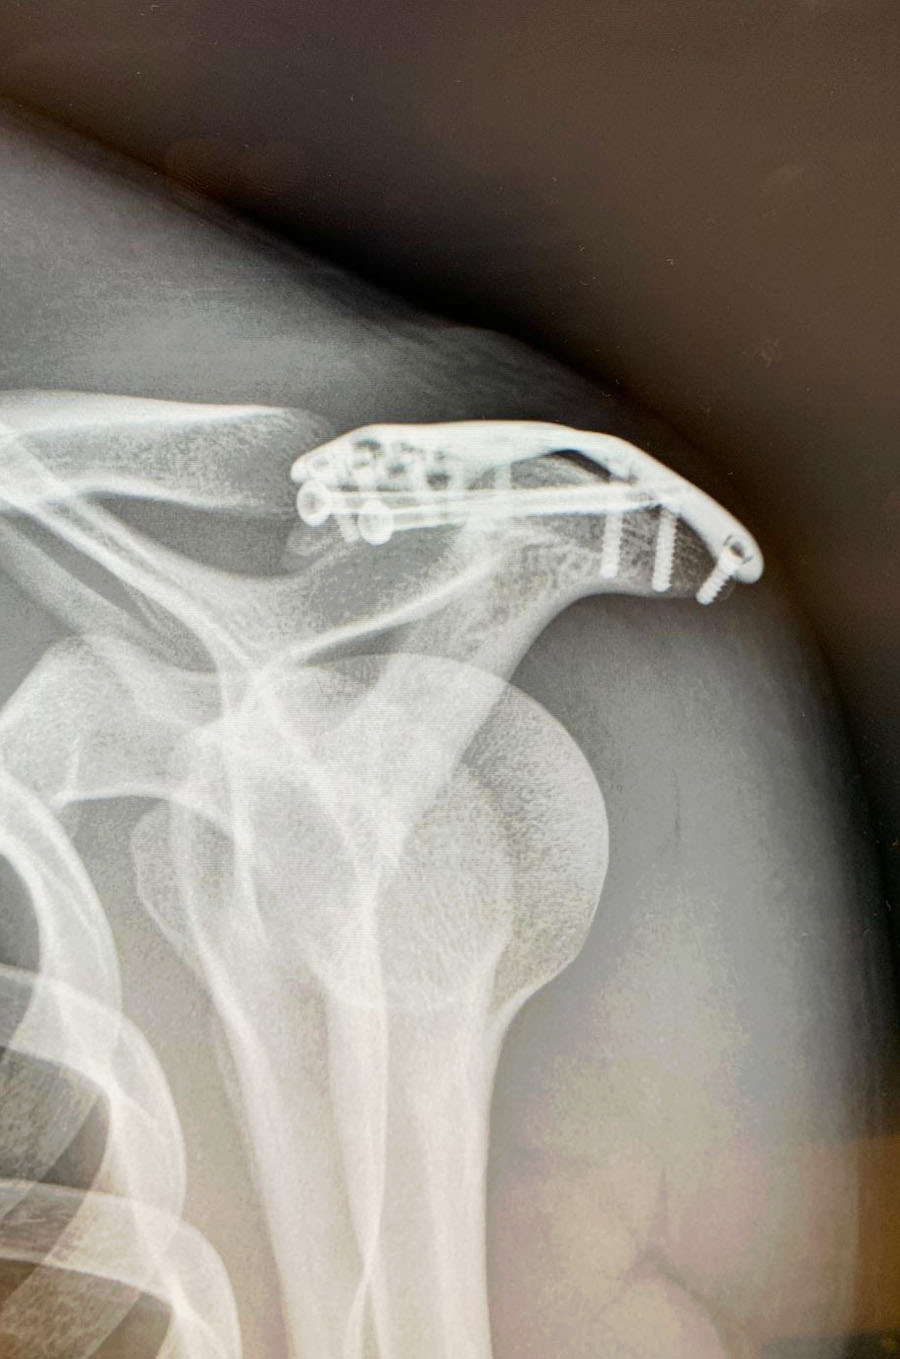

Hard-Enduro-Spezialist Dieter Rudolf musste doch unter’s Messer. Der am zweiten Offroad-Tag der “Red Bull Romaniacs” erlittene Bruch des Schulterdachs hat sich nicht von alleine ausreichend zusammengeschoben. Die Fuge war zu groß. Darum folgte der Niederösterreicher dem Rat mehrerer Ärzte uns ließ sich am Universitätsklinikum St. Pölten operieren. Der Bruch wurde mit zwei Schrauben und einer Titanplatte fixiert. Nach dem ersten Kontrolltermin ist der KTM-Pilot zuversichtlich. Es wurden keine Muskeln oder Bänder verletzt, die Operation ist gut verlaufen. Jetzt braucht es vor allem Zeit, Dieter Rudolf muss zumindest zwei Monate lang Ruhe geben.

Dieter Rudolf: “Die erste Kontrolle hat gezeigt, dass in der Schulter alles so aussieht, wie es sein soll. Allerdings war ich schon überrascht, welch großer Eingriff das war. Die ersten Tage danach waren auch wirklich schmerzvoll. Mittlerweile wird es von Tag zu Tag besser. Allerdings muss ich Ruhe geben, der Arm muss absolut geschont werden. Etwa einen Monat lang muss ich im wahrsten Sinn des Wortes komplett still halten. Danach beginnt dann die Physiotherapie. Ich muss auch hier geduldig bleiben. Mein persönliches Wunschziel ist aber, in etwa zwei Monaten wieder mit leichtem Konditionstraining beginnen zu können. Insgesamt blicke ich optimistisch auf die nächsten Wochen und möchte mich beim Ärzteteam in St. Pölten sehr bedanken!” (hubert lafer, c. panny)